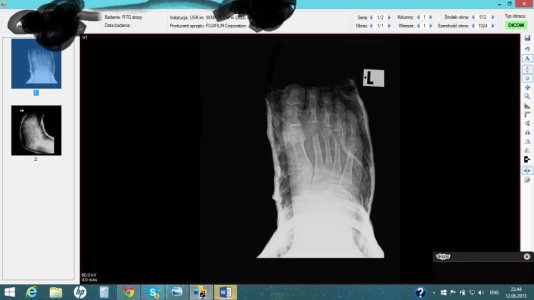

Здравствуйте, мне 19. Рост 150см вес 49, 2 недели назад играла фрисби и повернула ногу, думала ничего серьезного врач приходила сказала связки, спустя 1,5 недели пошла в больницу где мне сделали рентген и написали, что у меня перелом 5-ой плюсневой кости (это написано на польском перевела через переводчик), поставили гипс, сказали через недельку в другую больницу съездить. Сегодня друг забрал мой рентген, посмотрите пожалуйста, ничего серьезного, долго мне придется носить гипс, так как через 5 дней у меня поездка, можно мне ходить? иногда наступаю дома на ногу мне не больно ходить еще. Посмотреть вложение 12228